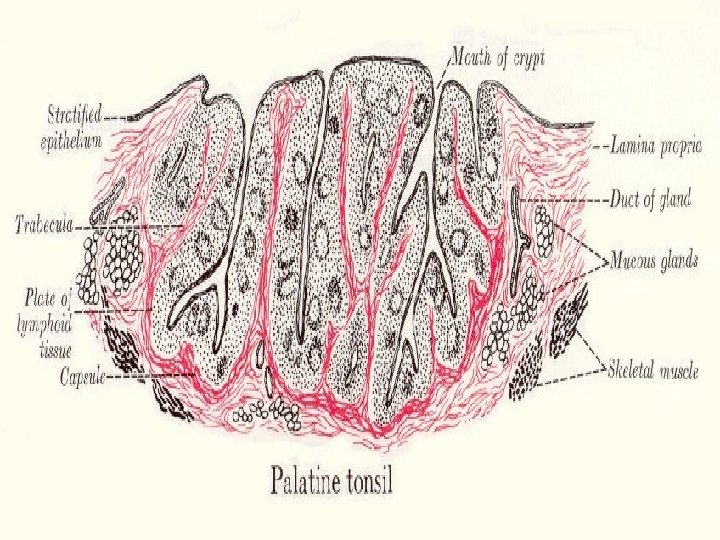

TONSILS These incompletely encapsulated lymphoid aggregates contain many lymphoid nodules; they underlie the mucous membranes (epithelial lining) of the mouth and pharynx. Together with the diffuse subepithelial lymphoid tissue that connects them to form a ring, they guard the common entrance to the digestive and respiratory tracts. The 3 types, palatine tonsils, the pharyngeal tonsil, and lingual tonsils, differ in number, epithelial covering, presence (or absence) and number of epithelial invaginations or crypts, and presence (or absence) of a definitive partial capsule. Most specific structures: epithelial linings, lymphatic nodules under the epithelium with lymphatic infiltration and crypts.

Palatine Tonsil